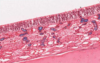

Where in the body might you find this epithelium?

- Inside the gallbladder

- Inside the mouth

- Lining the inside of the small intestine

- Lining the large airways

- Lining the outside of the small intestine

5.Lining the outside of the small intestine. This is a simple squamous epithelium, single layer of flattened cells with cylindrical/elliptical nuclei of the type found lining the outside of the intestine.